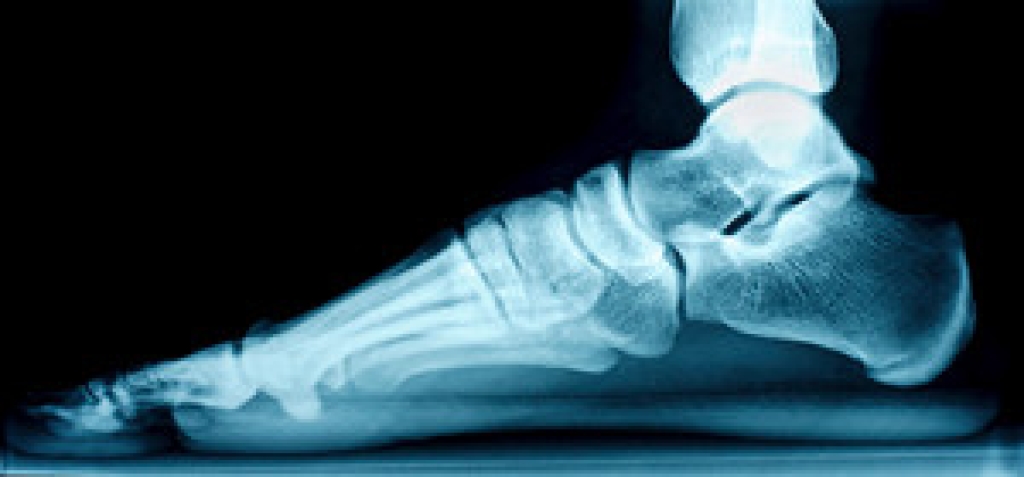

Dealing with Stress Fractures of the Foot and Ankle

Stress fractures occur in the foot and ankle when muscles in these areas weaken from too much or too little use. The feet and ankles then lose support when walking or running from the impact of the ground. Since there is no protection, the bones receive the full impact of each step. Stress on the feet can cause cracks to form in the bones, thus creating stress fractures.

What Are Stress Fractures?